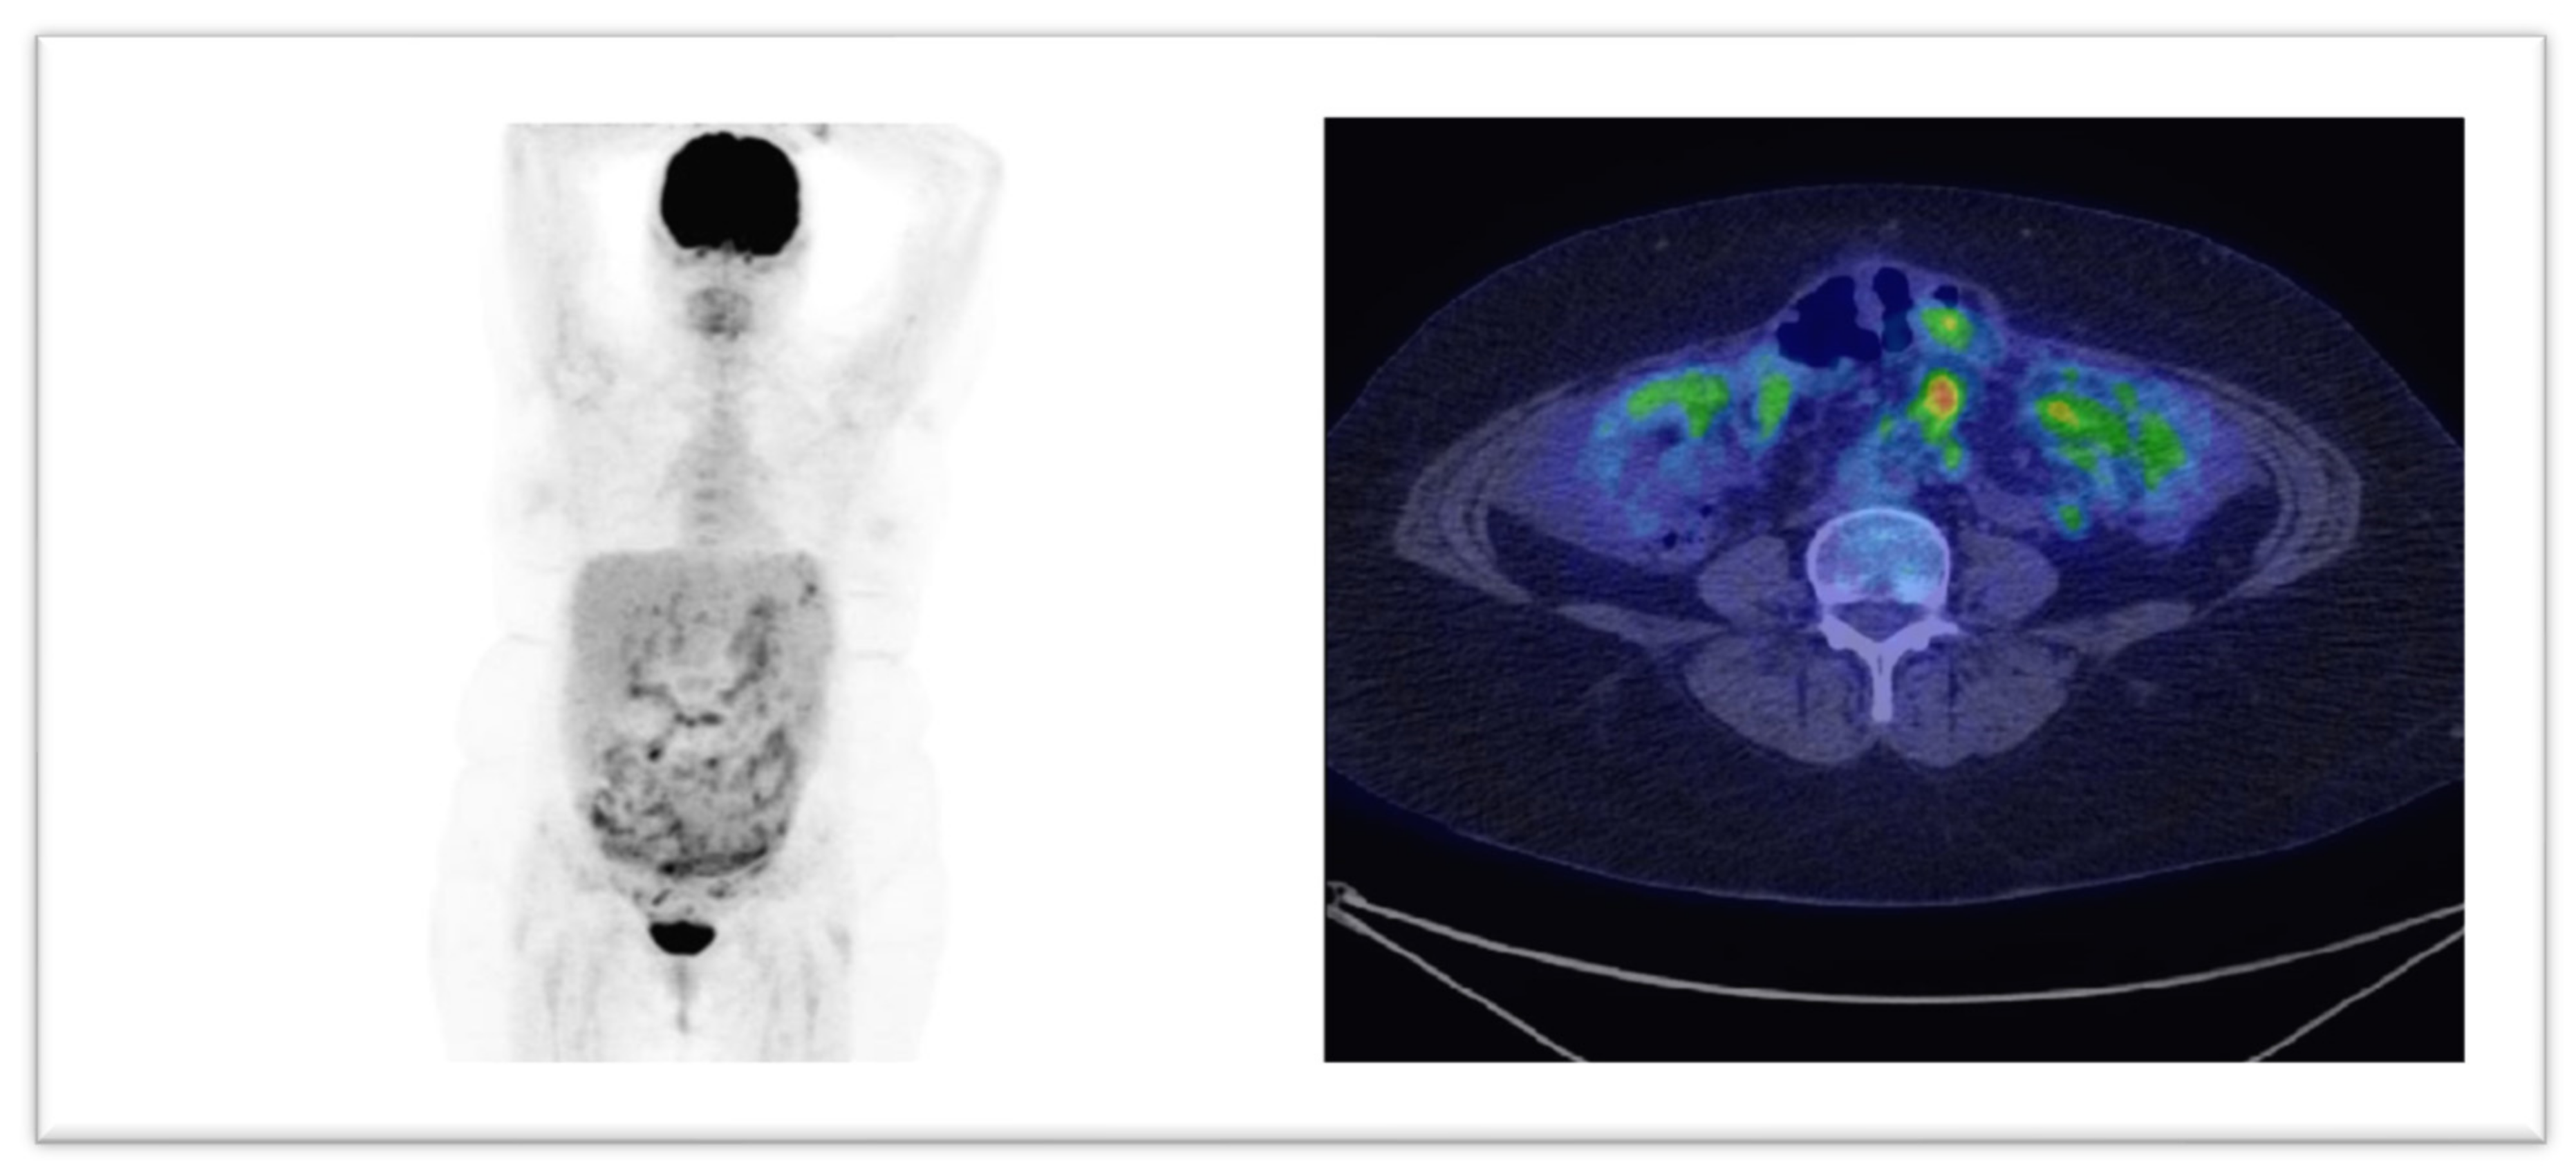

In Figure 4 and Figure 5 we display two cases where, based on PET/CT scans, the therapies had major changings. The modified treatment strategies occurred in our group, are presented in Table 3.

Figure 5.

MIP and axial images from a 18F-FDG PET-CT scan, revealing peritoneal carcinomatosis, in patient with a CA-125 serum level of 642 U/mL. After the investigation, the type of chemotherapy was changed (paclitaxel to topotecan).